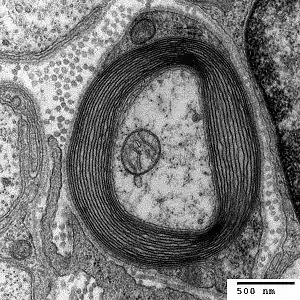

Vertebrates

Myelin is considered a defining characteristic of the jawed vertebrates (gnathostomes), though axons are ensheathed by a type of cell, called glial cells, in invertebrates.[16][17] These glial wraps are quite different from vertebrate compact myelin, formed, as indicated above, by concentric wrapping of the myelinating cell process multiple times around the axon. Myelin was first described in 1854 by Rudolf Virchow,[18] although it was over a century later, following the development of electron microscopy, that its glial cell origin and its ultrastructure became apparent.[19]